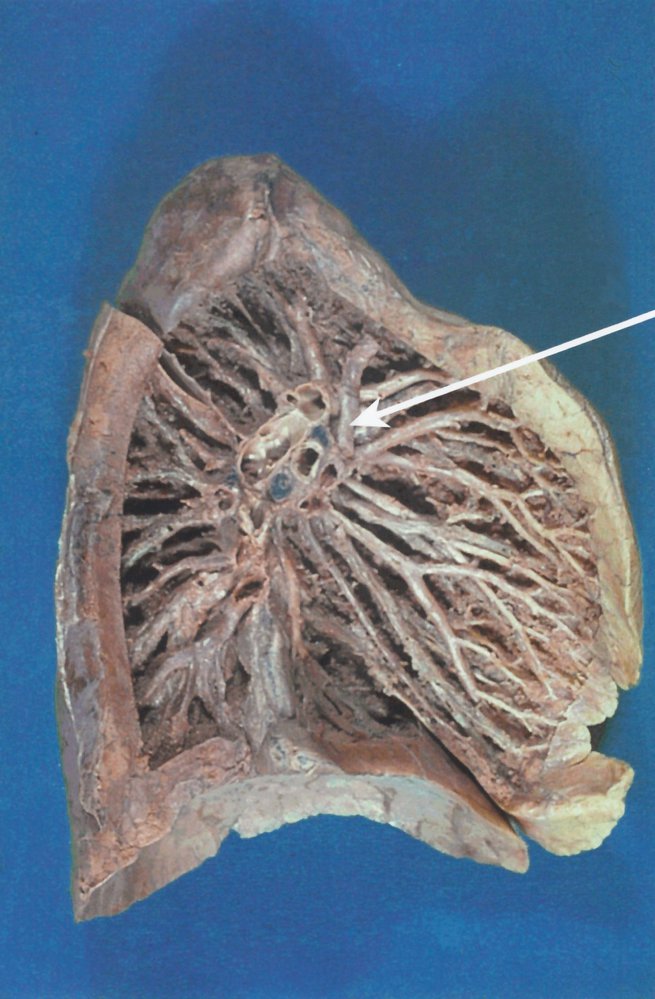

• Hilum of the lung: the point of attachment of the lung to the lung root, which serves as the entry and exit site of the primary bronchi, pulmonary arteries and veins, bronchial arteries and veins, pulmonary nervous plexus, and lymphatics of each lung

• Bronchopulmonary segments

• Segments of lung tissue that are supplied by a segmental bronchus and a segmental branch of the pulmonary artery.

• They are surrounded by a connective tissue septum (intersegmental septum), which encloses a branch of the pulmonary vein.